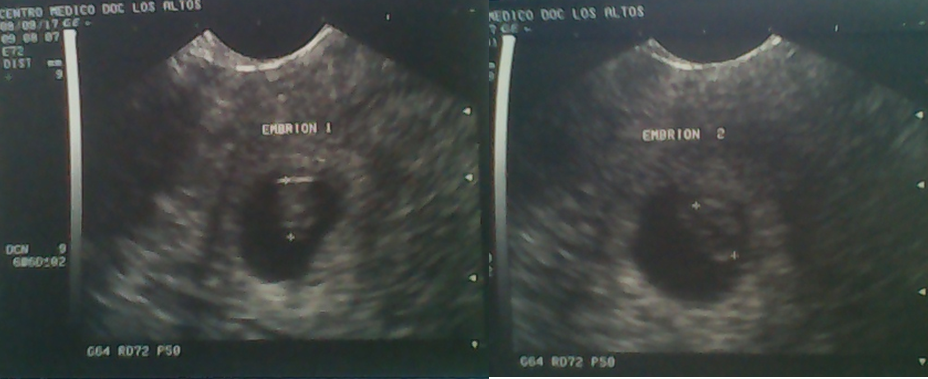

De hecho, yo definiría ese día como el segundo día más aterrador de mi vida, pero ¿Por qué el segundo?, bueno, sigan leyendo y lo sabrán. Resulta que esas semanas nos dedicamos a la realización de exámenes para confirmar el embarazo, sin embargo no habíamos podido ir al Obstetra, así que no teníamos ningún ecograma de confirmación del embarazo, hasta que a principios del mes de agosto del 2017, mi pareja fue a la consulta acompañada por mi mamá (por razones laborales yo no pude ir) y finalmente se confirmó la información con un eco, sin embargo, dicho eco vino con una pequeña sorpresa…¡eran gemelos!.

Las fotos de los dos embriones, el día de hoy no estoy seguro si quería o no que fueran gemelas xD.